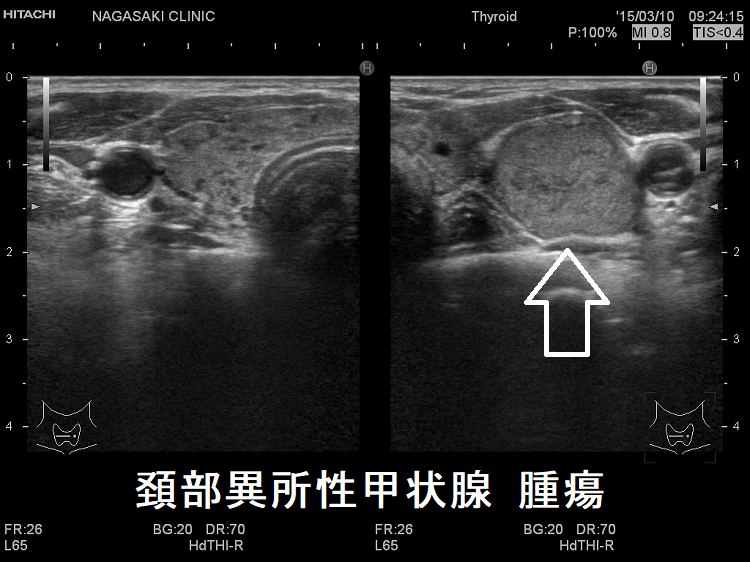

頚部異所性甲状腺(腫瘍)

時に、異所性甲状腺が腫瘍化している場合もあるため注意が必要です。腫瘍化が疑われる場合は穿刺細胞診の適応になりますが、濾胞性腫瘍なら良悪性の判定は困難です。また、異所性甲状腺が腫瘍化したものでなく、他臓器がんからのリンパ節転移の可能性もあるので要注意。

ケース①

頚部異所性甲状腺 腫瘍

頚部異所性甲状腺(腫瘍);異所性甲状腺は、本体の甲状腺と同じ組織の場合、腫瘍化している場合の2通りがあります。

写真の頚部異所性甲状腺は濾胞性腫瘍

同様に頚部異所性甲状腺が良性濾胞腺腫だった報告があります。[Int J Surg Case Rep. 2017;40:94-96.][Otolaryngol Head Neck Surg. 2004 Dec;131(6):1019-21.]

甲状腺乳頭癌だった報告もあります。[Int J Surg Case Rep. 2021 Dec;89:106628.]